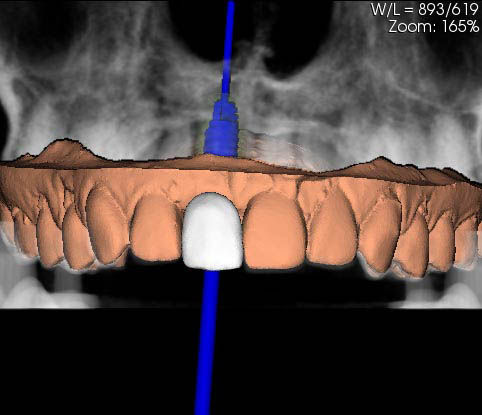

Matching between the stl file of the model scan and the DICOM file to obtain a prosthetically guided positioning.

Lateral image after the planning: the software allows the implant to be positioned by verifying the correct prosthetic emergence and angle in respect of the vestibular wall.